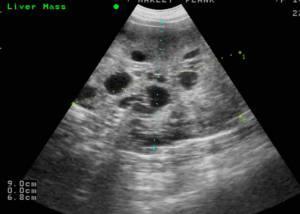

Los resultados in vitro se confirmaron tanto en modelos de ratón como en muestras humanas de HCC. “Cuando se analizaron los niveles de CXCR4 en los tejidos de los pacientes se ha observado que altos niveles de esta proteína se correlacionan siempre con la sobreactivación de la vía de TGFb y, lo más interesante, estos pacientes tenían un fenotipo de células tumorales menos diferenciados, y potencialmente más agresivos. Por otra parte, CXCR4 se encuentra preferentemente en láreas de invasión tumoral “, explica Fabregat